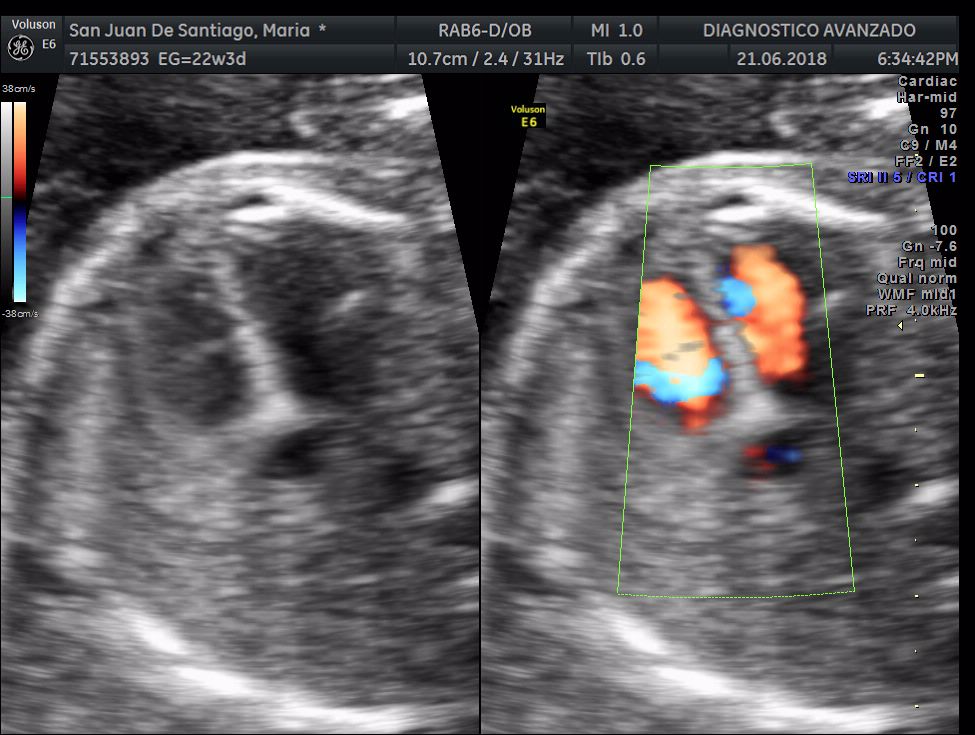

¡Hola a todos! Hoy hemos ido a hacer la tradicional ecografía 3D de la niña, os dejamos todo el material (aunque es un poco demasiado).